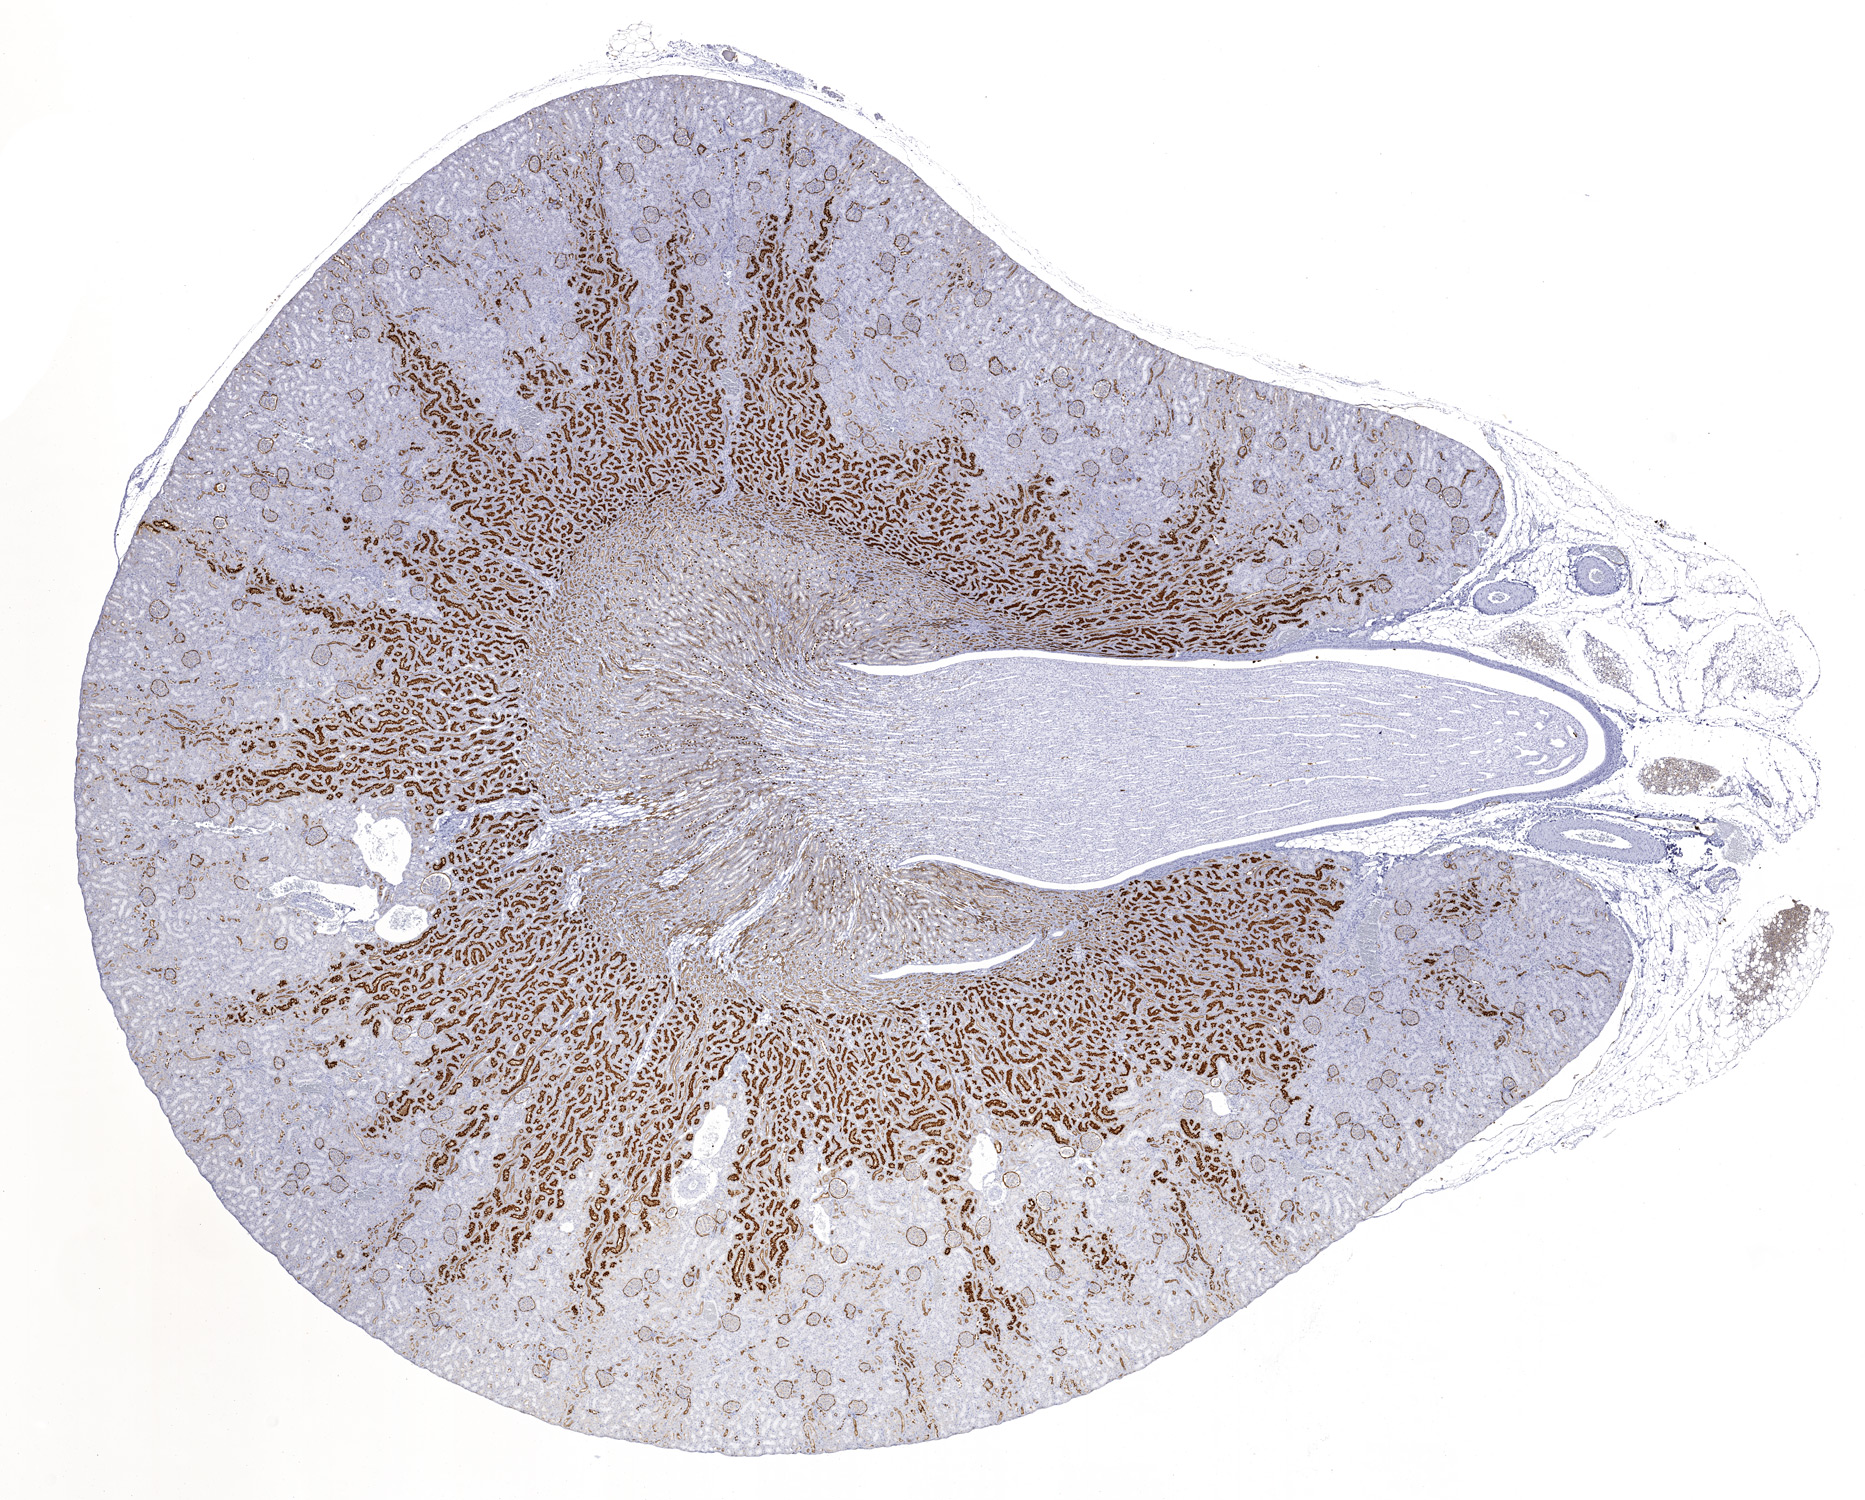

CD10: Immunoperoxidase staining of formalin-fixed, paraffin-embedded rat kidney showing cell membrane of the brush border in epithelial cells.